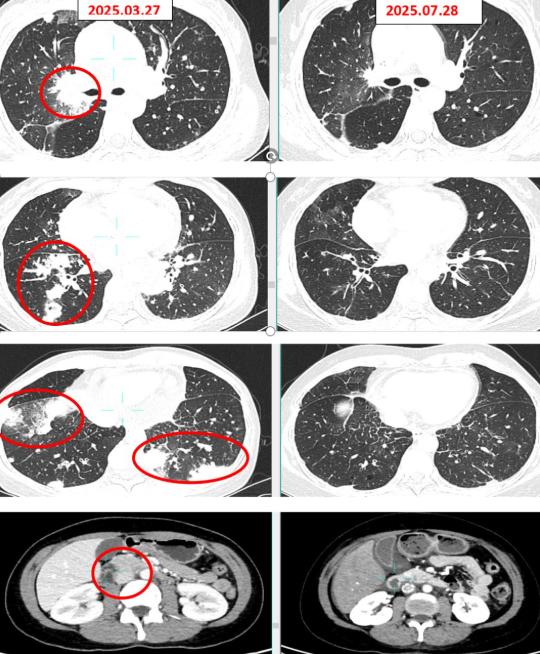

医生立刻针对性地使用NTRK抑制剂恩曲替尼,进行精准靶向治疗,没想到,奇迹真的发生了——用药仅仅3天,她身上的转移病灶就明显缩小,胸闷、乏力的症状也快速缓解,后续虽然因为药物副作用调整过方案,但在医生的细心照料下,肿瘤一直控制得很好。

如今,距离陈女士确诊晚期肺癌,已经过去一年多,她不仅稳稳熬过了当初“不到3个月”的生死关,病情稳定,生活质量也提高了不少。